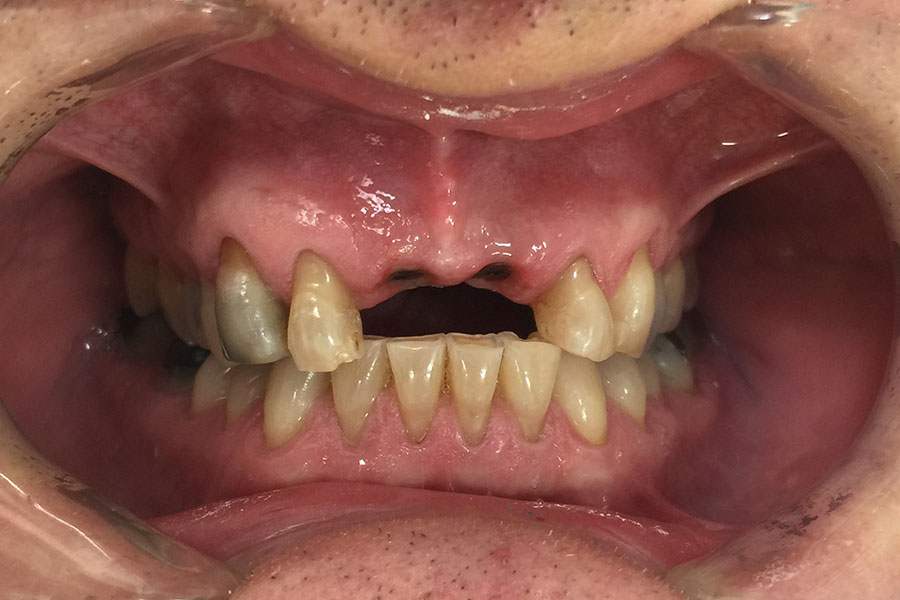

Andrew lost two front teeth while playing football about 40 years ago.

He wore a removable metal partial denture. These teeth were finally restored with two dental implants to support the teeth individually.